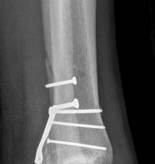

Image

Standard orthogonal radiographs (anteroposterior and lateral) are sufficient for initial diagnosis, but they routinely underestimate the complexity of partial articular fractures. A high-resolution computed tomography (CT) scan with two-dimensional multiplanar reformats (coronal and sagittal) and three-dimensional surface rendering is considered the standard of care.

CT imaging is critical for:

1. Identifying the exact location and size of the articular fragments.

2. Detecting central articular depression that is obscured by the cortical rim on plain films.

3. Mapping fracture lines extending into the diaphysis.

4. Planning the surgical approach to ensure direct access to the primary fracture line.